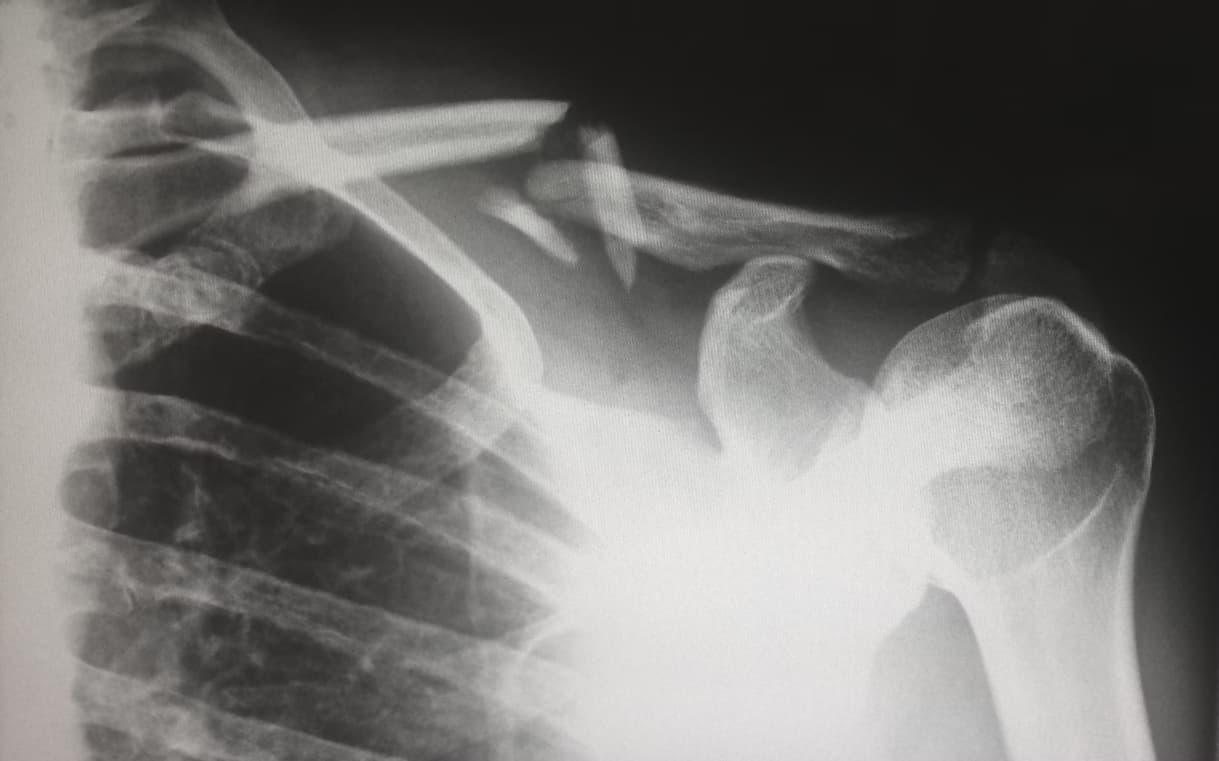

3. 회전근개 손상 (S46.0)

- 어깨 통증의 원인 중 하나, 초음파 + 주사 치료 빈번

- 수술 없이도 약물·주사·물리치료 실비 적용

- 초음파 진단 후 치료까지 연결되면 거의 100% 보장